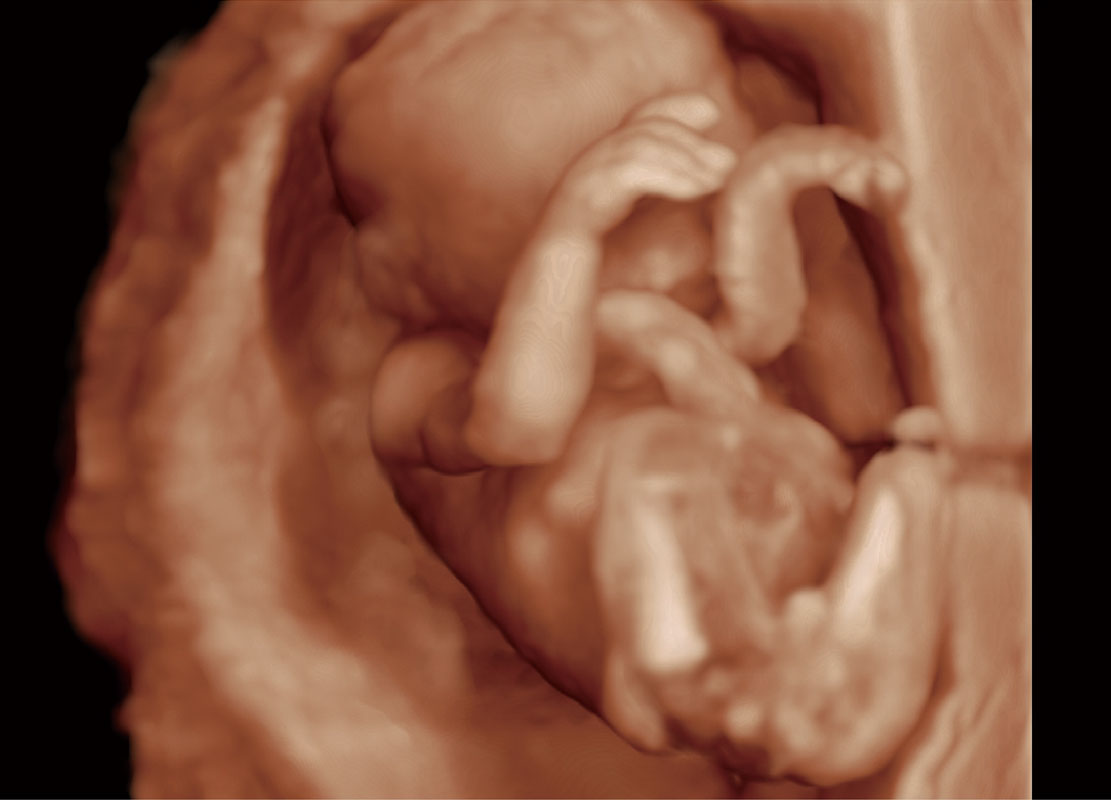

P60提供简单易学易用的高端诊断工具,为您中晚孕筛查提供快速清晰的解剖信息。

S-Fetus能够助您在实时扫查过程中自动识别标准切面、自动测量并录入报告。一个按键,即可快速、高效地获取胎儿生理指标,简化您的产科检查操作。